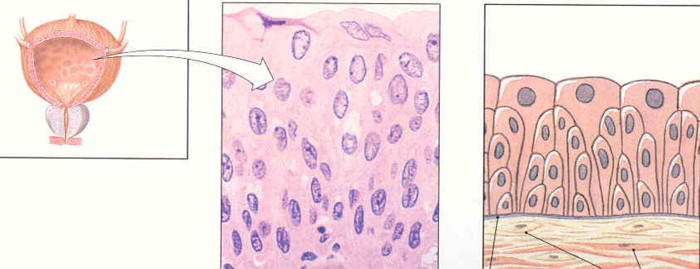

3. Transitional = many layers of cells of differeing shapes